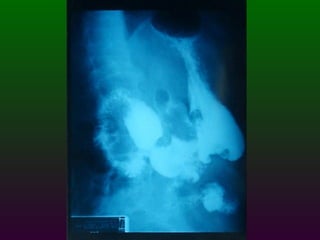

SEGD ENFERMEDADES DEL ESTÓMAGO Y DUODENO DIVISIÓN ANATÓMICA DEL ESTÒMAGO CARDIAS  FONDO CUERPO  ANTRO  PÍLORO

SEGD ENFERMEDADES DEL ESTÓMAGO INFLAMACIÓN NEOPLASIAS: Pólipos benignos Carcinoma Linfoma Leiomiomas TRASTORNOS DIVERSOS: Gastritis atrófica Crónica:   Gastritis hipertrófica   Gastritis cáustica   Vólvulos

SEGD ENFERMEDADES DELESTÓMAGO Y DUODENO DIVISIÓN ANATÓMICA DEL ESTÒMAGO CARDIAS FONDO CUERPO ANTRO PÍLORO

SEGD ENFERMEDADES DELESTÓMAGO INFLAMACIÓN NEOPLASIAS: Pólipos benignos Carcinoma Linfoma Leiomiomas TRASTORNOS DIVERSOS: Gastritis atrófica Crónica: Gastritis hipertrófica Gastritis cáustica Vólvulos